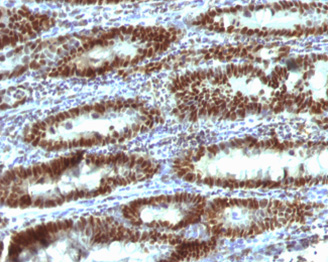

TOX Antibody: TOX (thymocyte selection-associated high mobility group (HMG) box protein) is a member of the HMG box family of DNA-binding proteins and likely plays a role in the regulation of T-cell development. It is a 526 amino acid nuclear protein and the expression of TOX is upregulated by pre-T cell receptor (pre-TCR) and TCR activation in immature thymocytes. TOX-mediated positive selection is associated with up-regulation of RUNX3 and is calcineurin dependent. TOX-dependent transition to the CD4+CD8 stage is required for development of class II major histocompatibility complex-specific T cells.